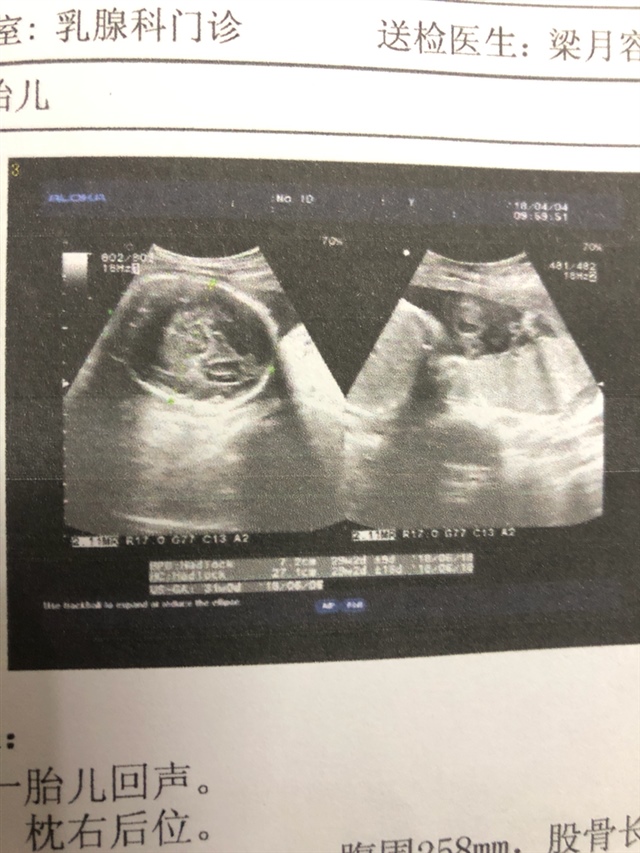

产前检查 B超